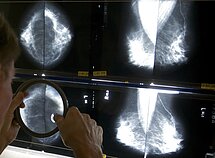

Krūties vėžio prevencijos programa skirta moterims nuo 50 iki 69 metų (imtinai), kurioms kartą per 2 metus gali būti atliekama mamografija. Pasak NVI Prevencinių programų koordinatorės, gydytojos radiologės dr. Rūtos Briedienės, šis tyrimas yra krūties ištyrimo rentgenu būdas, leidžiantis aptikti net kelių milimetrų darinį krūtyje. Tai neskausmingas, saugus ir efektyvus tyrimas.

Krūtų tomosintezės ir kontrastinės mamografijos tyrimus skiria gydytojas radiologas, dažniausiai tikslinant pakitimus krūtyse, matomus mamogramose ar ultragarsu. Tai tam tikros mamografinio tyrimo modifikacijos, kurios paprastai gretinamos su kitais tyrimais, bei atliekamos po mamografijos, esant neaiškiai diagnozei.

Kai kuriose šalyse krūties tomosintezė atliekama ir profilaktiškai vietoj mamografijos, esant tankiai liaukai. Lietuvoje tyrimą gali paskirti gydytojas specialistas, kartais šie tyrimai skiriami patikslinimui, atlikus mamografiją pagal patikros programą. Tyrimui reikalingas siuntimas.